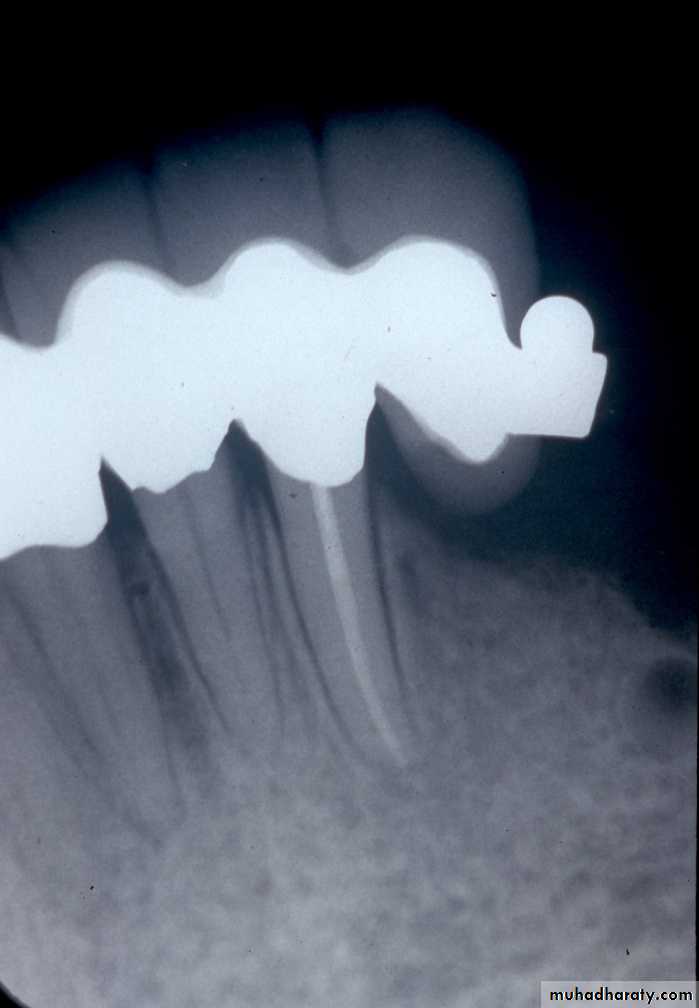

Extracoronal Attachments

• Positioned entirely outside the crown contour ; therefore, the normal tooth contour is maintained & the possibility of devitalizing a tooth is reduced in comparison to the intracoronal variety.

- Due to versatility and robust design, extracoronal attachments are among the mostly commonly used attachments both in the precision and semi-precision varieties.UNFAVORABLE ATTACHMENT APPLICATIONCANTILEVERING EFFECT

excessive cantileveringexcessive stress

failure of abutment teeth

Ceka

If we have Kennedy Class I (Bilateral distal extension), using of Rigid extracoronal attachment with un-splinted abutments.

This will cause over-Stress on the distal abutment teeth